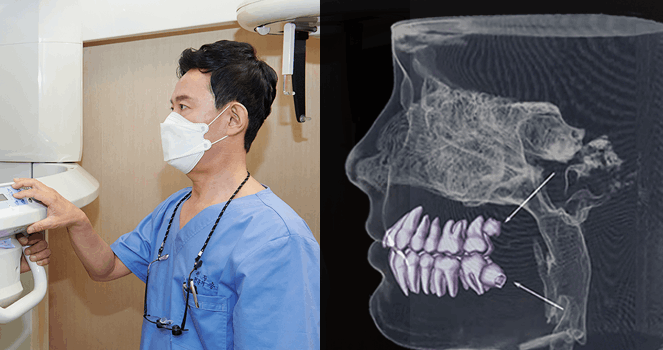

진단부터 다른 ‘청담뷰 AI DIGITAL’ 시스템

3D CT, RAY FACE로 촬영한 3차원 데이터를 통해

뼈, 잇몸, 신경을 통합적으로 고려해 정밀 진단합니다.

3D CT 촬영 및 스캐닝을 통해 얻어진 환자의 정보를 바탕으로

컴퓨터로 모의 수술을 통해 최적의 임플란트 수술 위치를 설정합니다.